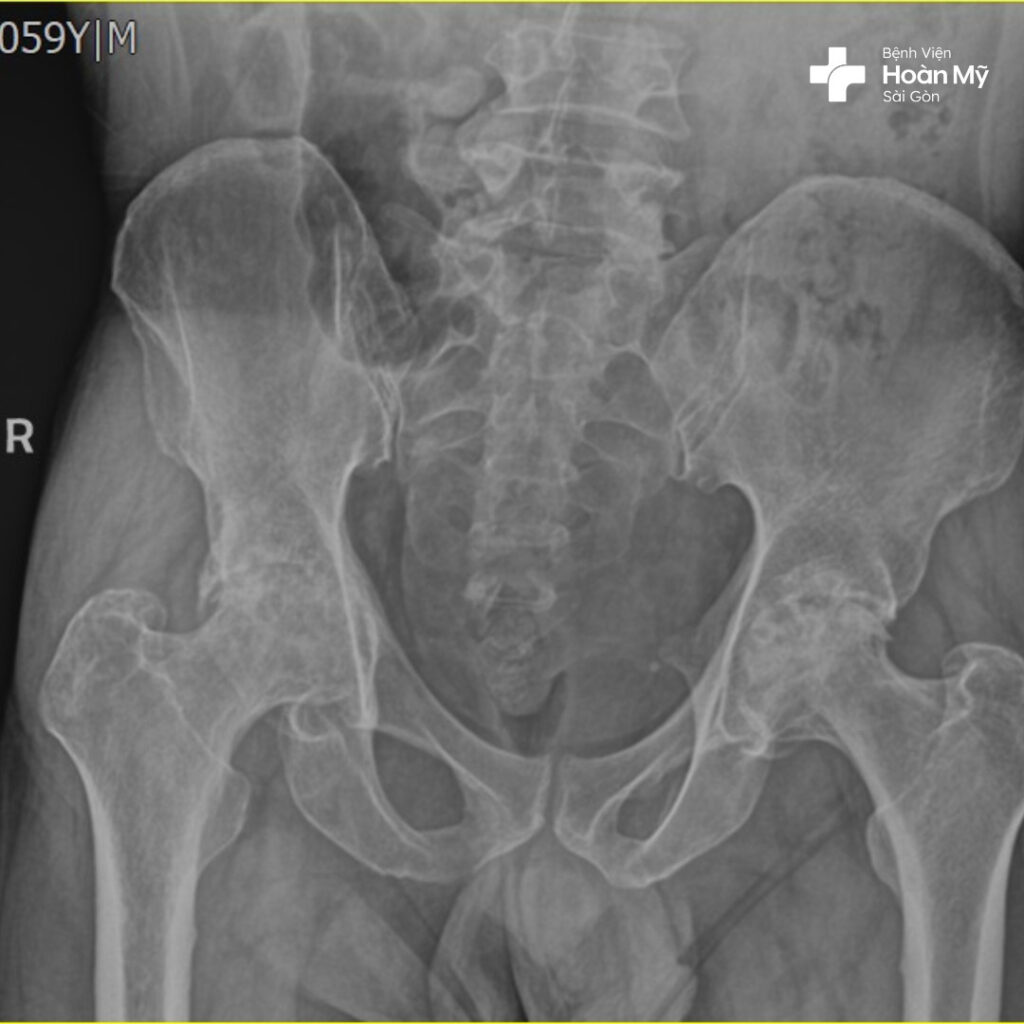

Hình ảnh X-quang trước khi phẫu thuật của ông Đ.

Chia sẻ về ca phẫu thuật, ThS.BS. Nguyễn Tấn Lãm – Trưởng Khoa Chấn thương chỉnh hình cho biết “bệnh nhân D. bị hoại tử cả 2 chỏm xương đùi trái và phải khá nặng. Kết quả chụp X quang cho thấy bệnh nhân bị hoại tử ở giai đoạn IV -V. Nếu phẫu thuật lần lượt từng chân thì bệnh nhân sẽ phải trải qua 2 cuộc phẫu thuật lớn. Đó sẽ là một trải nghiệm không hề dễ chịu”